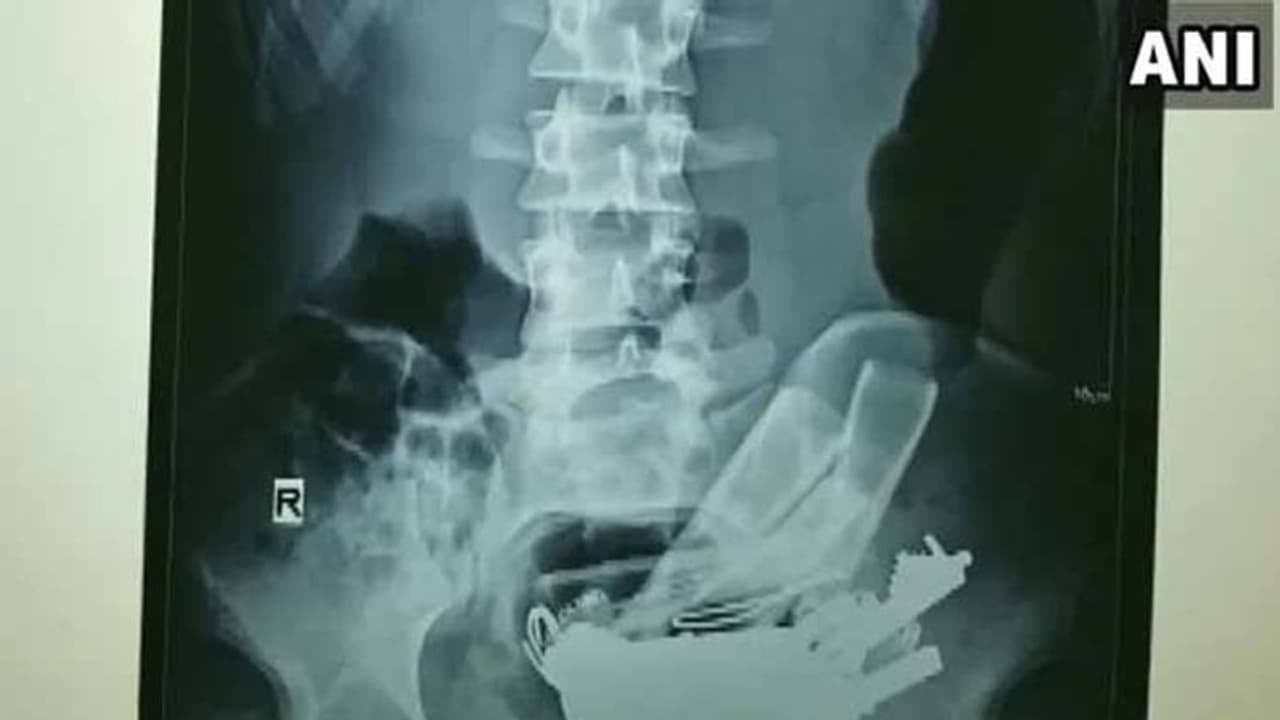

దీంతో అతను ఆస్పత్రికి వచ్చి వైద్యులను సంప్రదించాడు. అతని కడుపును స్కాన్ చేసి చూసిన డాక్టర్లకు లోహపు వస్తువులు కనిపించాయి. నలుగురు వైద్యులు సుమారు గంటన్నరపాటు శ్రమించి అతని పొట్టలో ఉన్న 80 లోహపు వస్తువులను బయటకు తీశారు.

వీటిలో తాళం చెవులు, మేకులు, నాణేలు ఉన్నాయి. సదరు రోగికి మతిస్థితిమితం లేకపోవడంతో ఆ వ్యక్తికి లోహపు వస్తువులు తినడం వ్యసనంగా మారిందని వైద్యులు తెలిపారు. కాగా ప్రస్తుతం ఆ వ్యక్తి ఆరోగ్య పరిస్ధితి నిలకడగా ఉందని వెల్లడించారు.